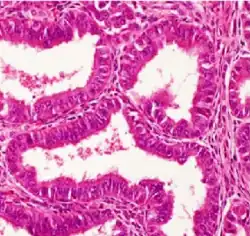

Histopathology of a well-differentiated endometrioid adenocarcinoma in the ovary | |

Light microscopy shows tubular glands, resembling endometrium.[8]